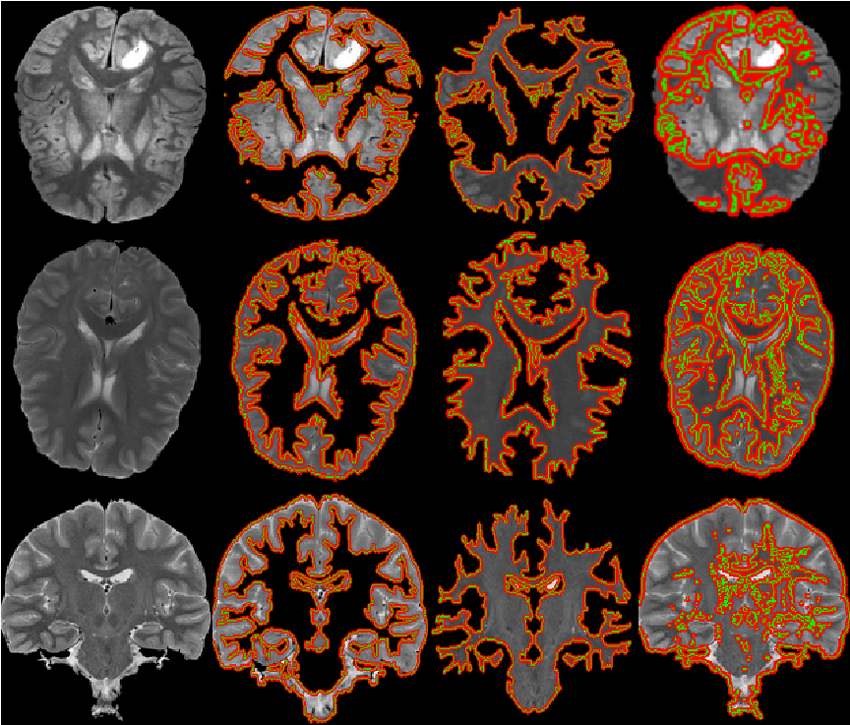

Pengolahan citra medis telah menjadi bidang yang semakin penting dalam dunia kedokteran modern. Salah satu teknik yang digunakan dalam pengolahan citra medis adalah segmentasi, yaitu proses pemisahan objek atau struktur yang ingin diidentifikasi dari latar belakang citra. Dalam kasus citra kepala MRI (Magnetic Resonance Imaging), segmentasi dapat membantu dokter dalam mendiagnosis dan memahami kondisi pasien dengan lebih baik. Salah satu metode yang digunakan dalam segmentasi citra kepala MRI adalah metode Active Contour.

Citra kepala MRI menyediakan informasi rinci tentang struktur otak, jaringan lunak, dan abnormalitas potensial lainnya dalam area kepala. Namun, citra-citra ini sering kali penuh dengan noise dan memiliki kontras yang bervariasi, membuat tugas segmentasi menjadi tantangan yang kompleks. Metode Active Contour, juga dikenal sebagai “Snake” atau “Level Set”, adalah salah satu metode yang membantu mengatasi tantangan ini.

Metode Active Contour bekerja berdasarkan konsep kurva kontinu yang bisa beradaptasi dengan kontur objek pada citra. Kurva ini dapat bergerak dan meregang untuk mengikuti kontur objek yang ingin di-segmentasi. Pada awalnya, kurva kontur diletakkan dekat dengan objek yang ingin di-segmentasi. Kemudian, kurva ini akan berusaha untuk mengubah bentuknya sehingga cocok dengan batas objek dalam citra. Proses ini dilakukan dengan meminimalkan energi internal dan energi eksternal yang terkait dengan kurva.

Segmentasi citra kepala MRI menggunakan metode Active Contour adalah teknik yang bermanfaat dalam bidang kedokteran di mana ketelitian dan akurasi sangat penting. Dengan kemampuannya untuk menyesuaikan diri dengan batas objek yang rumit dan beragam, metode ini membantu dokter dalam menganalisis citra kepala MRI dengan lebih baik, mendukung diagnosis yang lebih tepat, dan memfasilitasi perencanaan pengobatan yang lebih efektif. Meskipun memiliki beberapa tantangan, metode Active Contour tetap menjadi pilihan yang kuat dalam pengolahan citra medis.